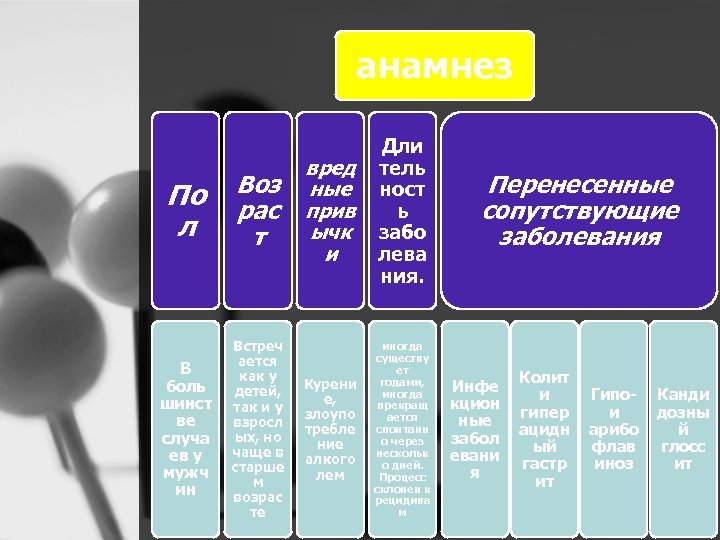

анамнез По л Воз рас т В боль шинст ве случа ев у мужч ин Встреч ается как у детей, так и у взросл ых, но чаще в старше м возрас те вред ные прив ычк и Дли тель ност ь забо лева ния. Курени е, злоупо требле ние алкого лем иногда существу ет годами, иногда прекращ ается спонтанн о через нескольк о дней. Процесс склонен к рецидива м Перенесенные сопутствующие заболевания Инфе кцион ные забол евани я Колит и гипер ацидн ый гастр ит Гипо и арибо флав иноз Канди дозны й глосс ит